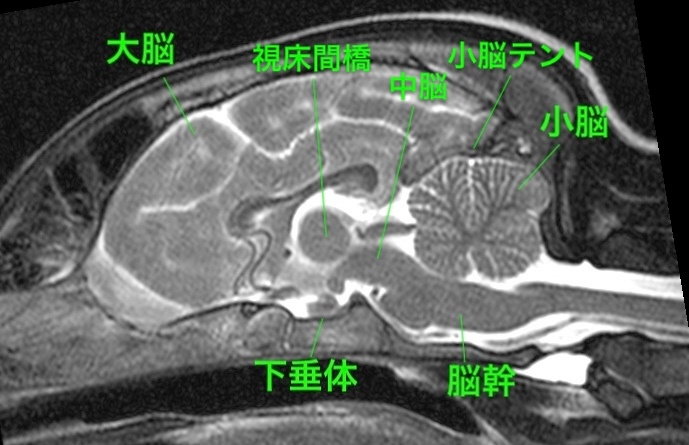

<症例情報> イタリアン・グレーハウンド12歳 未去勢の男の子 主訴:1ヶ月前に初めて発作を起こし、昨日2回目の発作を起こしたことで来院。麻酔をかけず…